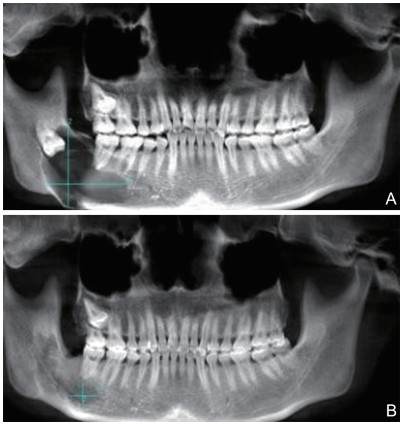

开窗减压术治疗颌骨囊肿的临床价值

金岚, 赵文妍, 阮妍, 钟林玲, 杨帆, 张国兴

2021, 19(11): 1851-1854. doi: 10.16766/j.cnki.issn.1674-4152.002183

1800 15

摘要:

目的  探讨开窗减压术治疗颌骨囊肿的价值。  方法  回顾性收集2015年6月—2019年5月在诸暨市人民医院口腔颌面外科诊治的88例颌骨囊肿患者的临床资料,依据手术方法不同分为研究组(开窗减压术,48例)与对照组(传统颌骨囊肿刮治术,40例),记录2组手术情况,比较2组手术前后囊腔病变情况,记录囊腔体积减少量、囊腔面积减少量和骨密度的变化;统计2组手术并发症发生情况,跟踪观察2组邻压牙髓坏死状况,比较随访复发率的差异。  结果  研究组的手术时间、术中出血量、术后住院时间分别为(29.83±2.18)min、(12.43±2.11)mL、(2.11±0.48)d,均显著少于对照组[(51.52±10.28)min、(52.34±2.99)mL、(4.72±0.52)d,t=-14.254、-73.191、-24.454,均P < 0.001]。研究组术后3、6、12个月囊腔体积减少量、囊腔面积减少量均多于对照组,骨密度值高于对照组(均P < 0.001)。研究组术后3个月并发症发生率(4.17%)低于对照组(25.00%,χ2=8.041,P=0.005)。研究组术后3个月邻近牙髓坏死率(0.00%)低于对照组(12.50%,P=0.039)。研究组随访复发率为0.00%,略低于对照组的7.50%,但组间差异无统计学意义(P=0.180)。  结论  开窗减压术治疗颌骨囊肿可减少术中出血量,缩小颌骨囊肿,促进囊腔修复,提高骨密度,减少术后并发症,降低邻近牙牙髓坏死发生率。